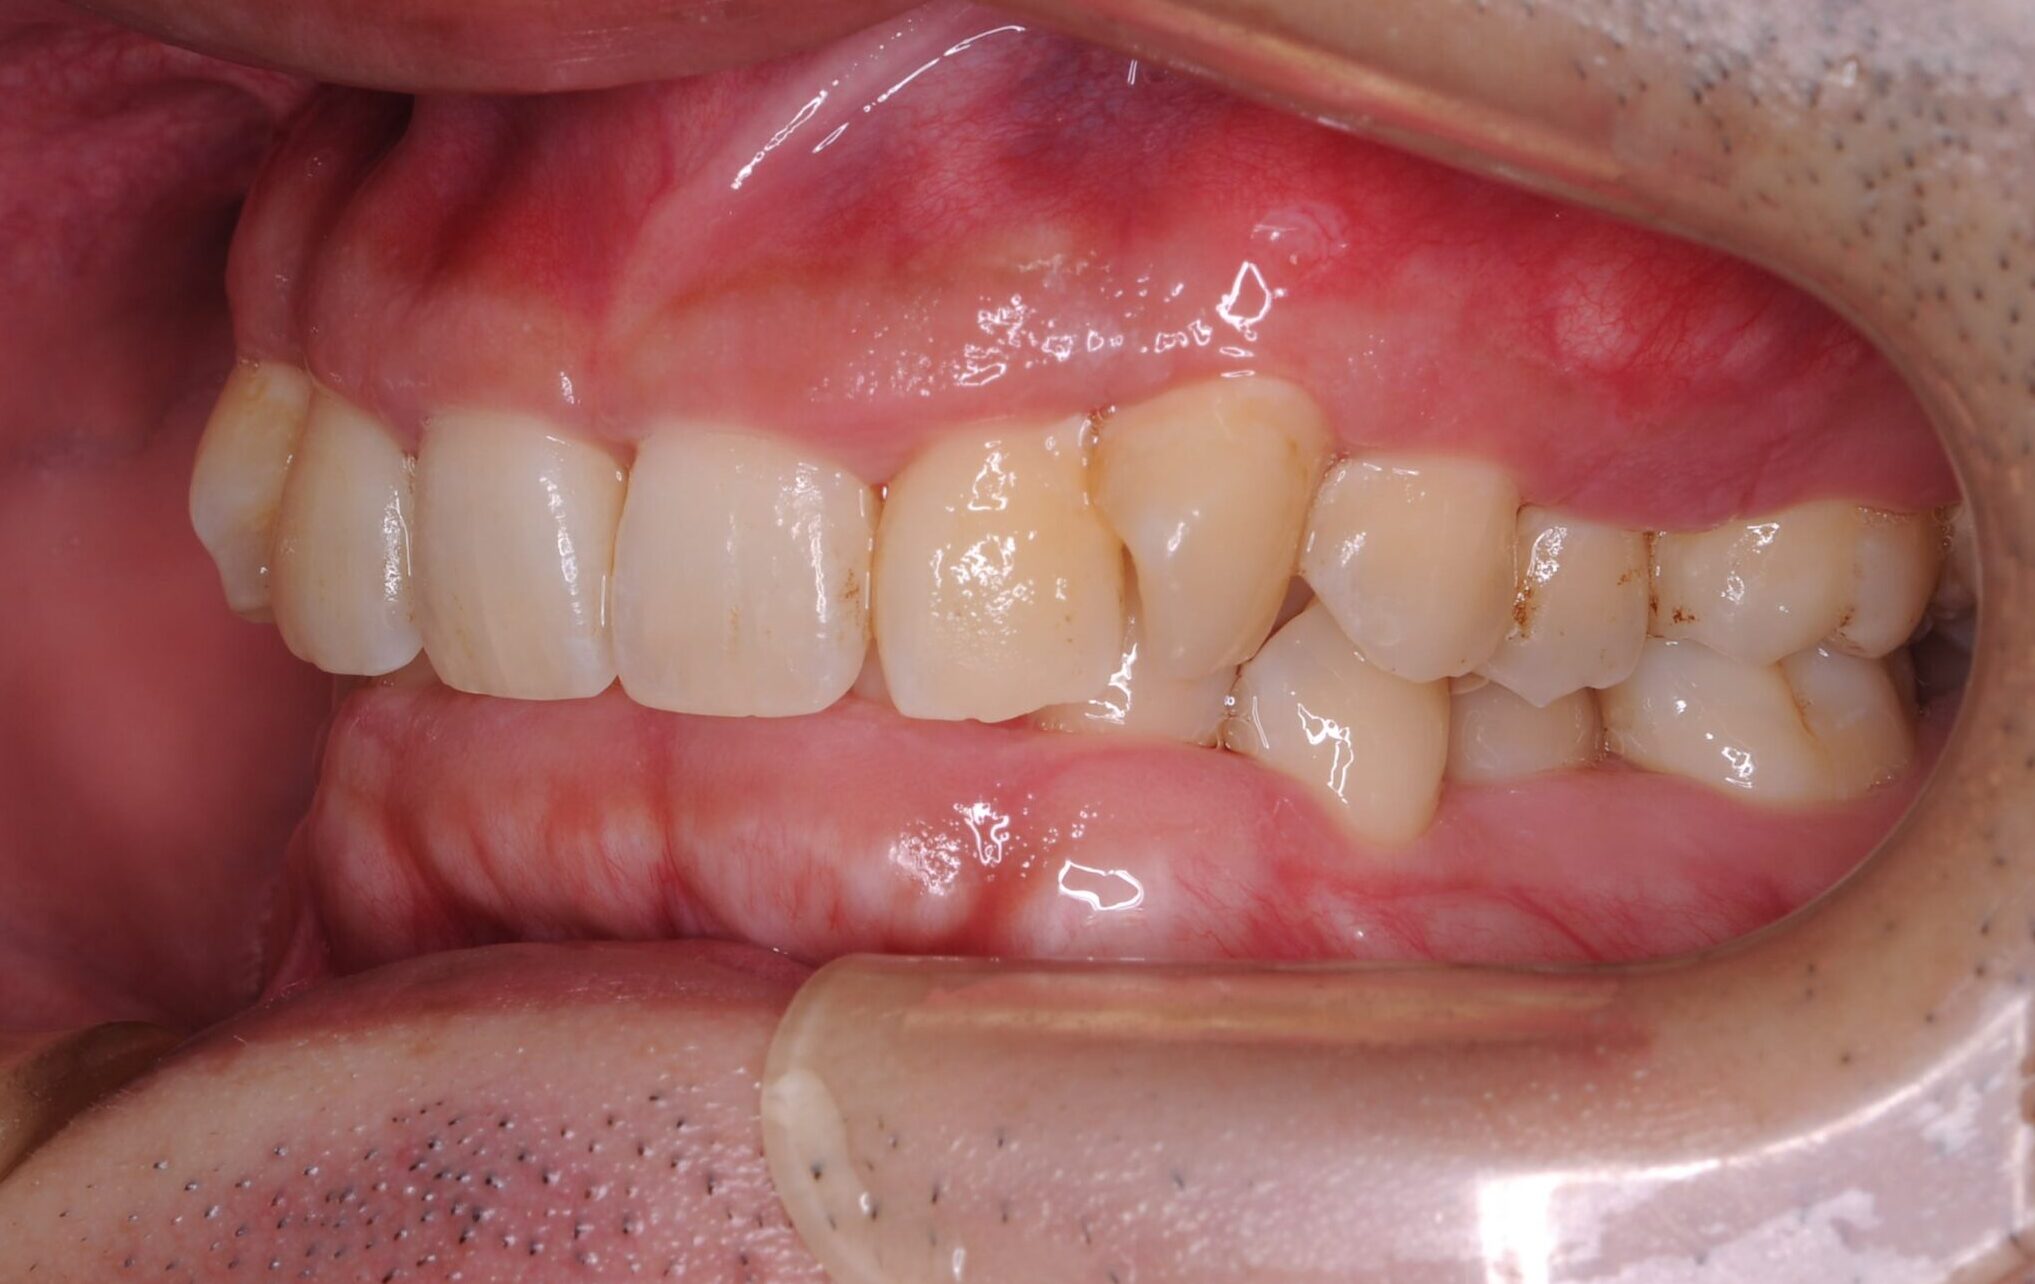

30代・男性

歯茎から出血、歯石除去|中等度に進行した歯周病

症例写真 before

中等度歯周病

歯医者が久しぶりなのでクリーニングをしてほしい、ということで来院されました。

レントゲン撮影、歯周検査などを行なった結果、全体に多くの歯石付着が認められる進行した中等度の歯周病であることが判明しました。ご本人も歯茎から出血することは気になっており、担当歯科衛生士から歯周病について説明を行いました。

今回は歯石の付着が広範囲に渡っており量も多いことから、歯科衛生士による歯周基本治療に加え歯科医師による外科手術も行うことで、徹底的に治療していくことになりました。